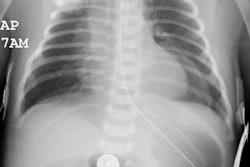

J Thorac Imaging 1992 Mar;7(2):62-77

Pulmonary involvement in collagen vascular disease: a review of the pulmonary manifestations of the Marfan syndrome, ankylosing spondylitis, Sjogren's syndrome, and relapsing polychondritis.

The pulmonary manifestations of collagen vascular diseases span an enormous

range of clinical and radiographic findings. The

breadth of these abnormalities is as diverse as the underlying diseases

themselves. A comprehensive discussion of pulmonary

involvement in four of these diseases, the Marfan syndrome, ankylosing

spondylitis, Sjogren's syndrome, and relapsing

polychondritis, is presented.